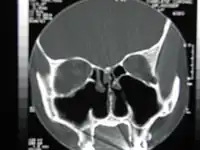

CT scan of the nose after total bilateral turbinectomy/turbinoplasty | |

A turbinectomy or turbinoplasty (preserving the mucosal layer) is a surgical procedure, that removes tissue, and sometimes bone, of the turbinates in the nasal passage, particularly the inferior nasal concha. The procedure is usually performed to relieve nasal obstructions.[1] In most cases, turbinate hypertrophy is accompanied by some septum deviation, so the surgery is done along with septoplasty.[2]